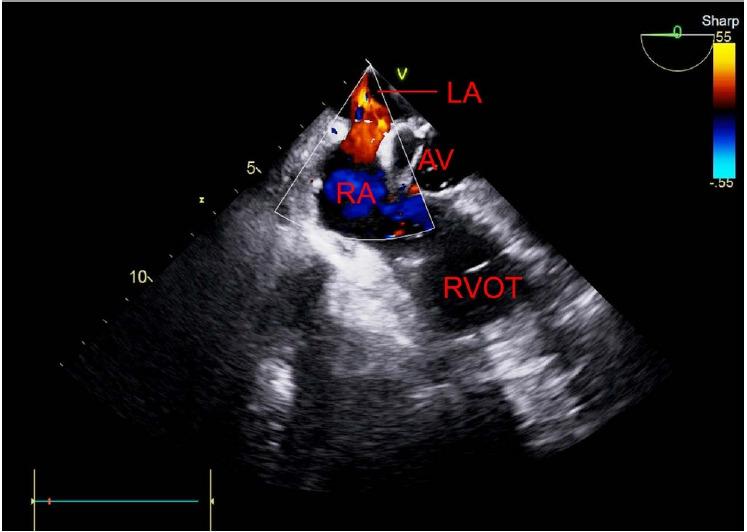

A 70-year-old male with hepatic cell carcinoma underwent laparoscopic hepatectomy. Though his vital signs were stable during the initiation of surgery, they became unstable during the procedure. The surgeon detected portal vein rupture, and transesophageal echocardiography was subsequently performed. A large amount of gas in the heart chamber and paradoxical embolism through a patent foramen ovale due to a right-to-left shunt were observed. We treated the symptoms, and the surgery was completed without any further issues.